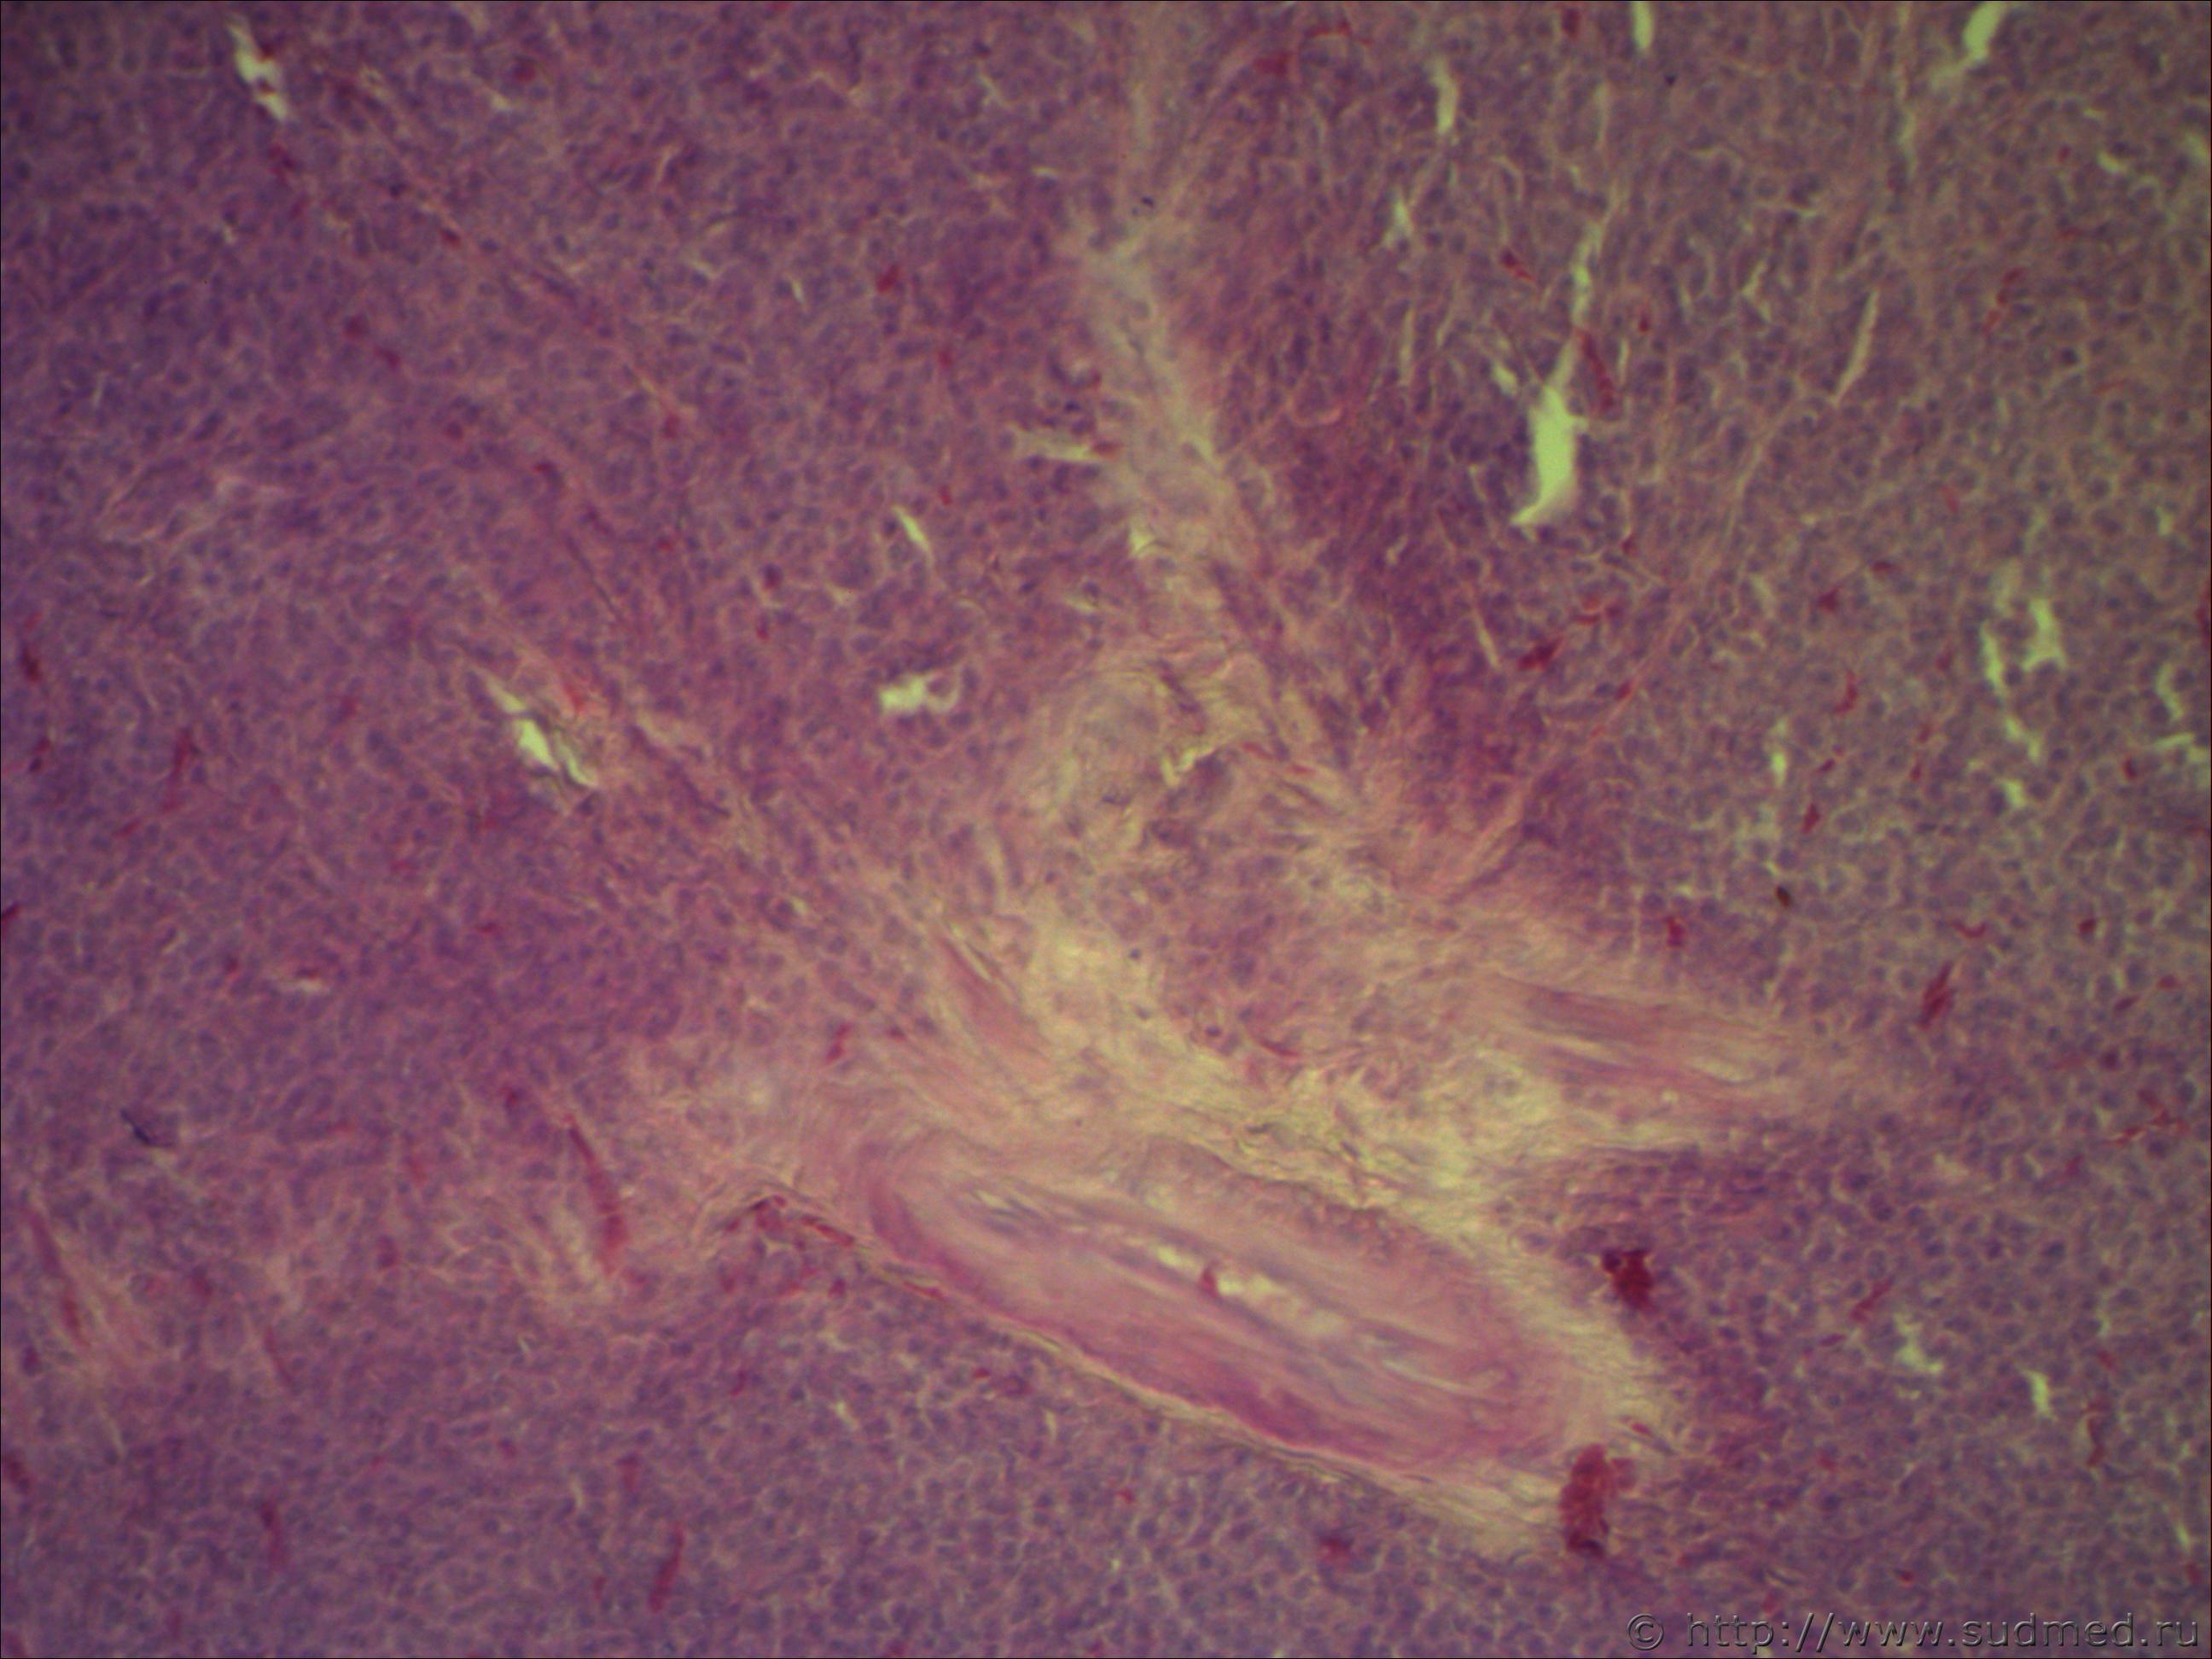

Н/о молочной железы

Похоже на беспигментную меланому.

Похоже на грибовидный микоз, либо на лимфоцитому(это мое мнение). В базальных клетках эпидермиса (на малом увеличении, где эпидермис четко ограничен)все таки меланомные пигменты видны, но без нарушения. Но видите как то резкости нет на фото.